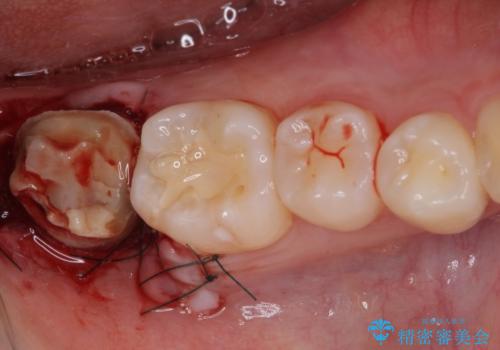

歯の高さが低く、かぶせものを安定して維持させることができないため、歯冠長延長術により歯の高さを増大させた上で、オールセラミッククラウンにて補綴することとしました。

クラウンが外れている期間も長く、虫歯が進行していたため、根管治療も行うこととしました。

- 外科手術のため、術後に出血、痛みや腫れ、違和感を伴います